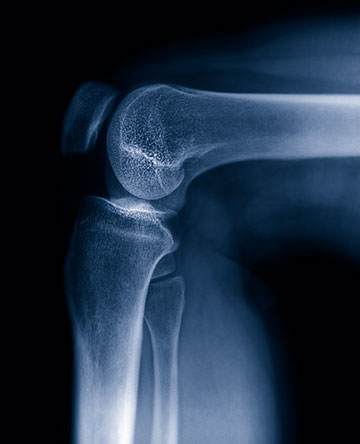

The knee is one of the most commonly damaged joints. Injuries range from overuse to arthritis and may occur in any age group. Common problems include meniscus and ligament injuries, pain related to the knee cap joint and arthritis. Treatment may include activity modification, physical therapy, injections, bracing, arthroscopic surgery, realignment procedures and knee replacement. Wellington’s Orthopedic Surgeons have expertise in both sports medicine procedures and in joint replacement surgery of the knee.